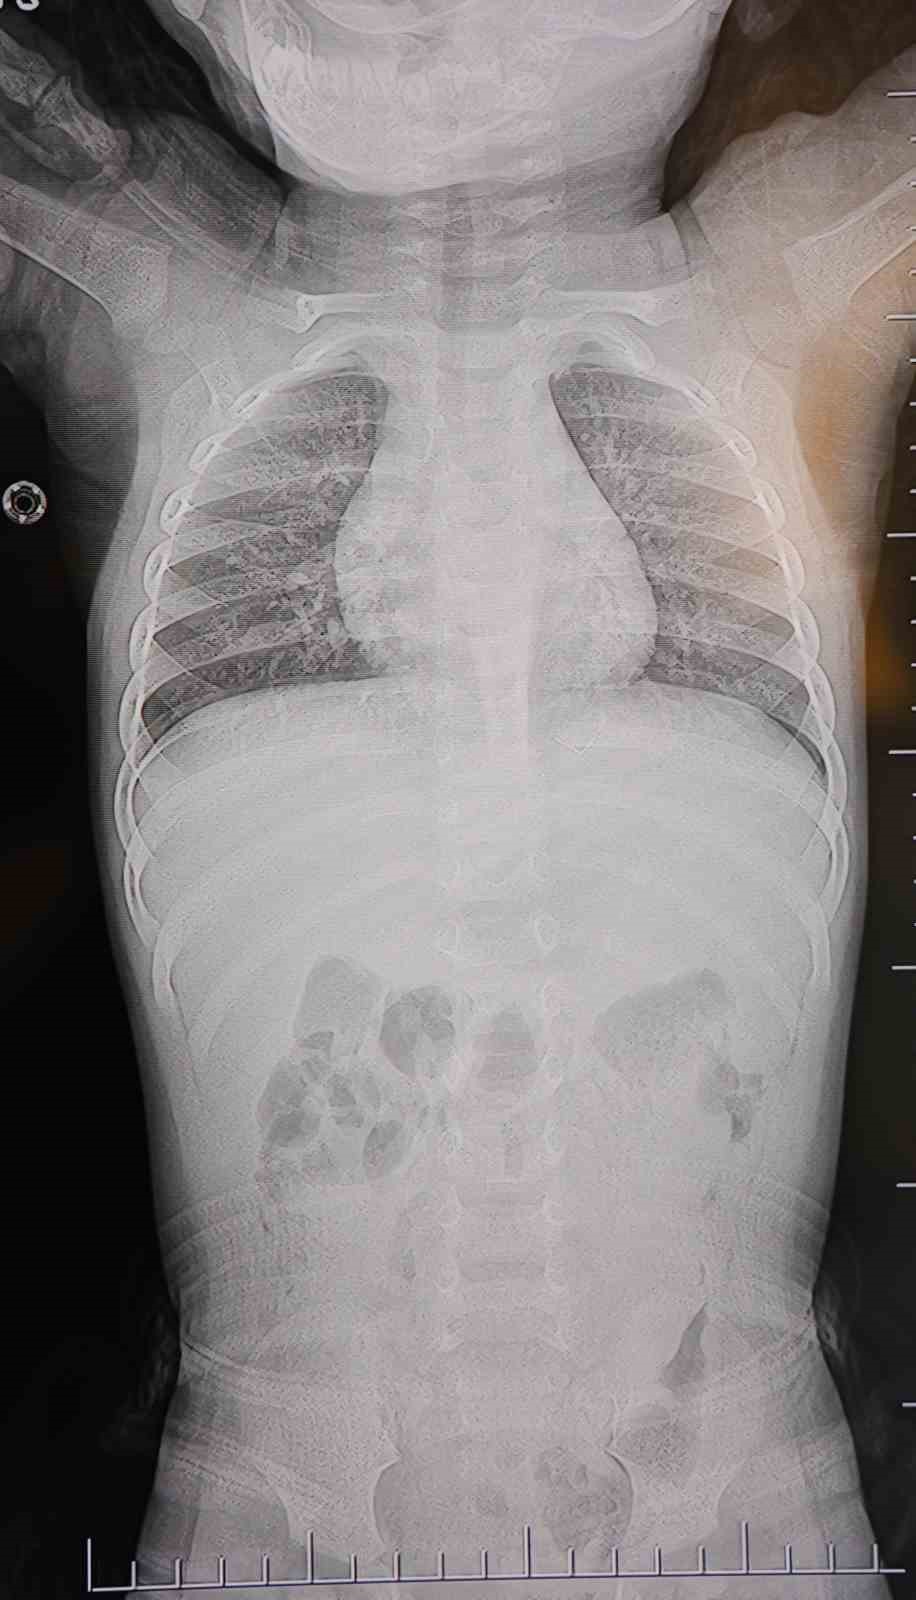

Alınan bilgiye göre, Kahramanmaraş’ta farklı ortopedi, çocuk cerrahisi ve beyin cerrahisi kliniklerine başvurusu yapılan bir yaşındaki bebeğin, sırt bölgesinde yabancı bir cisim olduğu ancak müdahalenin zor olduğu ve 8 yaşına kadar beklenmesi gerektiği bildirildi. Aile, bebekleri için son olarak HG Hospital’e başvurdu. HG Hospital Beyin ve Sinir Cerrahisi Uzmanı Prof. Dr. İdris Altun tarafından yapılan tetkiklerde, yabancı cismin cilt altında, omurilik kanalına yakın bir bölgede olduğu ve akciğer zarına doğru ilerlediği belirlendi. Hasta, genel anesteziye alınmadan, lokal anestezi ve sedasyon eşliğinde ameliyata alındı. Yapılan müdahalede yabancı cisim tamamen çıkarıldı. Çıkarılan cismin, ince zımba teline benzer metal bir tel olduğu ve yaklaşık 2 santimetre uzunluğunda bulunduğu tespit edildi. Hasta, aynı gün taburcu edildi.

Konuya ilişkin açıklama yapan Prof. Dr. İdris Altun, "Sırtında yabancı bir cisim olduğu söylenmiş ancak çıkarılamayacağı ve 8 yaşına kadar beklenmesi gerektiği ifade edilmişti. Bize başvurduğunda yaptığımız tetkiklerde, cilt altında, omurilik kanalına çok yakın ve akciğer zarına doğru ilerleyen bir yabancı cisim tespit ettik. Hastamızı tamamen uyutmadan, lokal anestezi ve sedasyon eşliğinde müdahale ederek lezyonu tamamen çıkardık. Çıkardığımız cismin ince zımba teline benzer, yaklaşık 2 santimetre uzunluğunda metal bir tel olduğunu gördük. Bu yabancı cisim alınmasaydı, bölgede enfeksiyon gelişebilirdi. Enfeksiyon sonucu omurilik kanalında ciddi hasarlar oluşabilir, çocuk büyüdükçe cismin hareket etmesine bağlı olarak omurilikte zedelenmeler meydana gelebilirdi. Ayrıca yana doğru ilerleyerek akciğer zarına ve akciğere batma riski vardı. Bu da enfeksiyona ve ilerleyen süreçte tümörle karışabilecek tablolara neden olabilirdi. Şu an hastamız gayet sağlıklı. Gerekli kontrolleri yaptık ve aynı gün taburcu ettik" dedi.